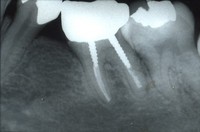

20〜39歳の歯やお口のチェックポイント

20〜39歳の歯やお口のチェックポイント 40歳から65歳のアンチエイジング歯科チェックポイント

40歳から65歳のアンチエイジング歯科チェックポイント